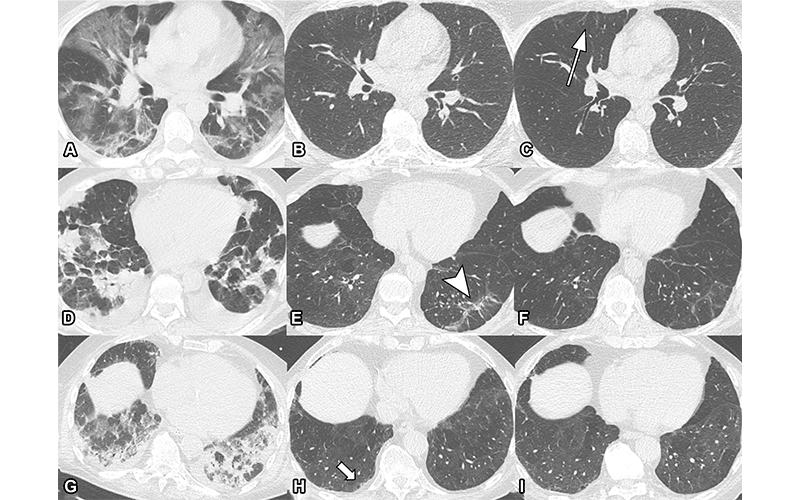

Serial non-contrast axial chest CTs of three study participants with prior COVID-19 pneumonia. Chest CT of a 44-year-old man (upper row, A-C) displayed extensive bilateral GGO and supleural reticulation during acute COVID-19 (A). At the 2-month follow-up almost complete resolution of GGO with residual subpleural reticulation in the middle lobe was noted (B). These subpleural reticulations (arrow) persisted up to one year after onset (C). Chest CT of a 68-year-old-man (middle row, D-F) demonstrated patchy bilateral consolidations, a subpleural arcade-like sign and pleural effusions during active infection (D). At the 2-month follow-up, a substantial improvement of OP pattern was noted with GGO and subpleural reticulation including arcade-like sign (arrowhead) in the left lower lobe (E). At the 1-year follow-up, further improvement was noticed. However, subtle reticulation and GGO could still be detected (F). Chest CT of a 79-year-old man (lower row, G-I) displayed bilateral consolidations and small areas of GGO while admitted to the ICU (G). At the 2-month follow-up, residual GGO and small subpleural microcystic changes (thick arrow) were noticed (H), which persisted up to 1 year after onset (I).

Luger et al, Radiology 2022; In Press, ©RSNA 2022